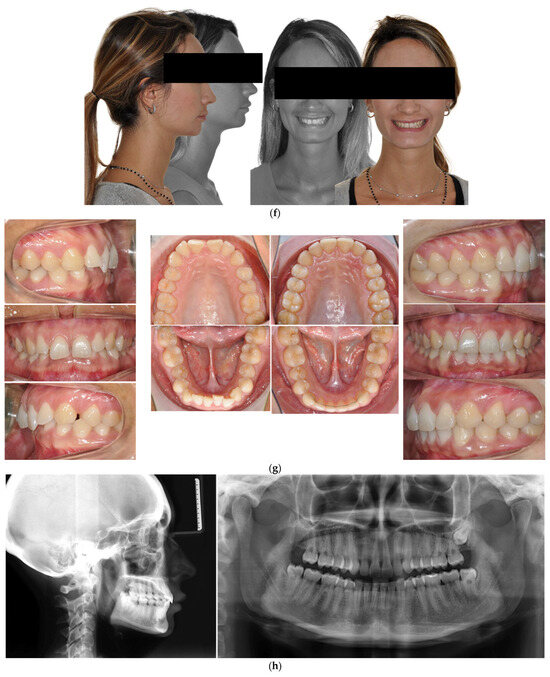

- Case 2: Class III with deep bite

4.2. Case 2: Class III with a Deep Bite